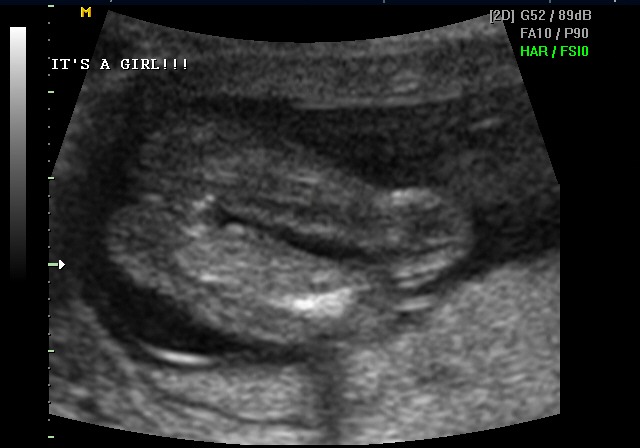

Ultrasound — It's a girl

It's a girl.